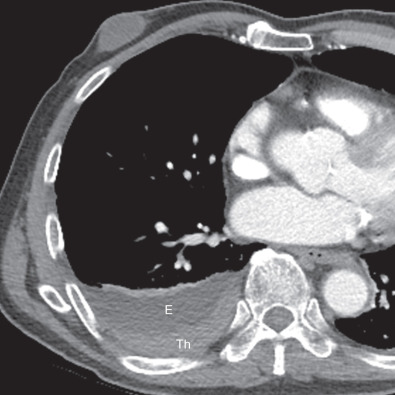

The characteristic presentation of pleural plaques on high-resolution CT consists of circumscribed areas of pleural thickening separated from the underlying ribs and extrapleural soft tissues by a thin layer of fat. Retired dock worker with history of multiple exposures to asbestos. Pleural plaques do not become malignant.

Pleural plaques were defined as focal areas of pleural thickening with soft tissue attenuation which could contain calcification typically located on the posterior wall of the lower half of the pleural spaces often in the paravertebral regions on the anterior wall between the third and the fifth costal interspaces andor on the diaphragmatic pleura. However there are a few rare cases in which pleural plaques are found near. From the history of breathlessness and the chest X-ray with characteristic pleural plaques and interstitial fibrosis it suggests that the patient has asbestosis.

Pleural plaques are the most common manifestation of asbestos inhalation and occur 2030 years after first exposure. Pleural plaques that form because of asbestos fibers are normally found in the parietal pleura the lining of the inner wall of the chest. Pleural plaques are seen in 314 of dockyard workers and in 58 of insulation workers.

The plaques are composed of fibrohyaline tissue and form within the parietal pleura manifesting with characteristic radiographic and CT findings Fig. Pleural plaques are areas of thickened tissue in the pleura around the lungs. The important distinguishing point is that asbestosis begins more centrally and dissipates peripherally following a centrifugal pattern.